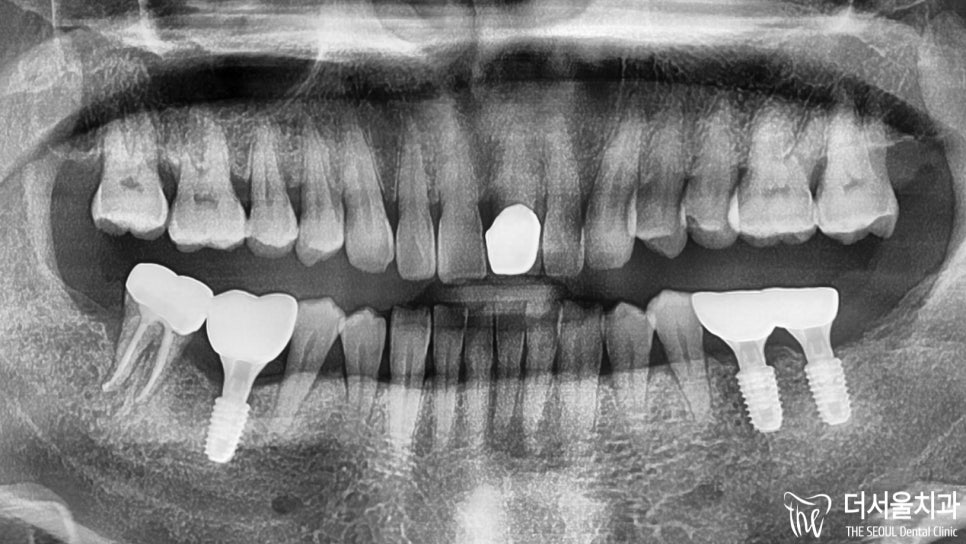

디지털임플란트 를 제일 먼저 하기로 했기 때문에

정확한 식립을 위한 분석을 시작했습니다.

빠져있는 아래 어금니 세 곳에

인공치를 심기로 했었는데요.

세 곳 모두 주변 조직 및 인접치와의 관계를

각각 파악하여 최적의 식립로를 설정했습니다.

이후, 미리 제작된 가이드를 사용하여

무절개 방식으로 단단하게 심어드렸습니다.

이제 결과를 보여드릴 차례네요.

모든 보철을 지르코니아를 사용하여

심미성을 한껏 더해주었습니다.